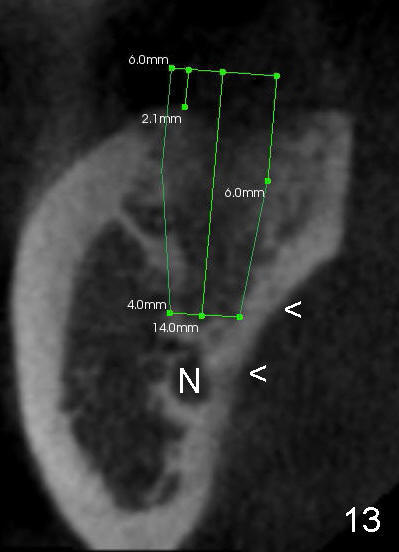

The submandibular (gland) fossa, or lingual (L) concavity (Fig.1 <), is more pronounced in the lower 2nd molar (7) that that of the first (6) (Fig.1 vs.2, 4 vs.3, the same patient). The lingual concavity may be mild (Type I, <2 mm depth, Fig.9-11), moderate (Type II, 2-3 mm, Fig.1,4, 12) and severe (Type III, >3 mm, Fig.13,14 (same patient)).

In addition, it is important to control the depth of the osteotomy. For freshly healed socket and immediately post-extraction socket, it should be safe to place a 11 mm long bone-level (Fig.15,16) or 14 mm gingival level (Fig.13,18) implant or less. For the same length, it appears safer to use a tapered implant (Fig.9,13,18) than cylindrical one (Fig.15,16).